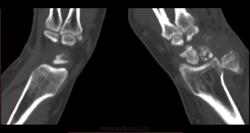

После 6-го коммента добавляю КТ. DICOM тут: http://files.mail.ru/A64E4C объём 14,5 МВ.

К большому моему сожалению, методом КТ не владею. Попробую описать то, что вижу, в надежде, что Вы поправите. Множественные полиоссальные очаги костной деструкции с достаточно четкими контурами (склеротический ободок?), местами с нарушением целостности кортикального слоя. В головчатой кости в деструктивном очаге плотная тень, похожая на секвестр. Полулунная фрагментирована соответственно ас/некрозу. Суставные щели сохранены, хотя соотношения костей запястья в горизонтальной плоскости выглядят не нормально. Мягкие ткани увеличены в обЪеме, дифференцировка структур по ладонной поверхности сохранена, по тыльной поверхности ближе к локтефой четкость теряется, на этом фоне непонятные мне включения. + отмечается расширение сосудистых теней. Остеомиелит и флегмона остаются у меня под большим сомнением. И характерных для нейротрофических нарушений напластований тоже не вижу (возможно, еще не срок?). При РА таких деструктивных изменений не встречала, и остеопороз под ?. Хотелось бы узнать Ваш вариант, уважаемая ЛГ.

Интраоссальные "секвестры" в запятье, а их два, это интраоссальные тофусы. Глыбчатые аморфные образования по плотности больше хряща, но меньше обызвествления, - это тофусы в мягких тканях. Кистовидные изменения костей запястья, с истончением коркового слоя и его частичным прерыванием - характерно для подагры.

Дословно не помню, примерно так: по рентгенограммам написала в заключении фрагментацию и асептический некроз полулунной кости, кистовидные просветления головчатой и трехгранной кости (деструктивные?). По КТ в заключении: признаки последствия болезни Кинбека, подагрические тофусы мягких тканей, подагрические изменения костей запястья.